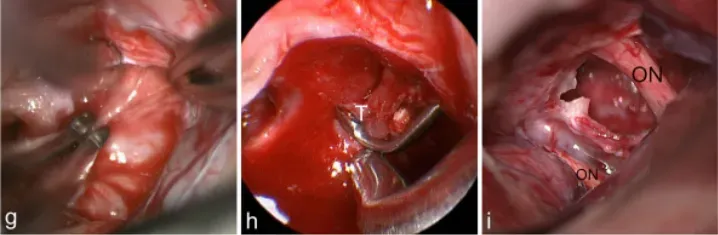

d图中,肿瘤(T)为通过右侧额外侧入路,暴露右视神经(ON)e图中,肿瘤包膜是用刀切开,f图显示钙化的肿瘤部分已被肿瘤切除

g图中,使用镊子的双向牵拉技巧解剖分离肿瘤;h图中,肿瘤(T)在30°神经内窥镜视野下正常显微镜难以显示;i图中,最终检查显示肿瘤全切除和视神经完整保留(ON)